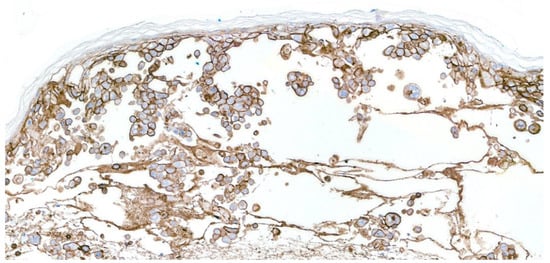

3.1. Varicella-Zoster Folliculitis

3.3. Herpetic Syringitis

3.4. Varicella-Zoster Vasculitis

3.5. Verrucous Varicella-Zoster Infection

3.6. Isotopic Response, Koebner’s Phenomenon, and Renbök’s Phenomenon